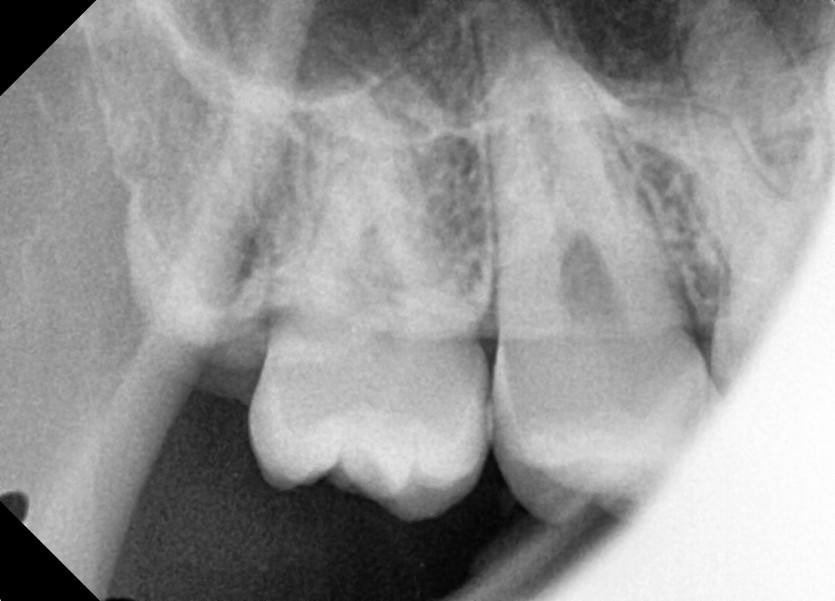

#18,48 사랑니 발치

구강 외과 전문의가 당일 발치했습니다.